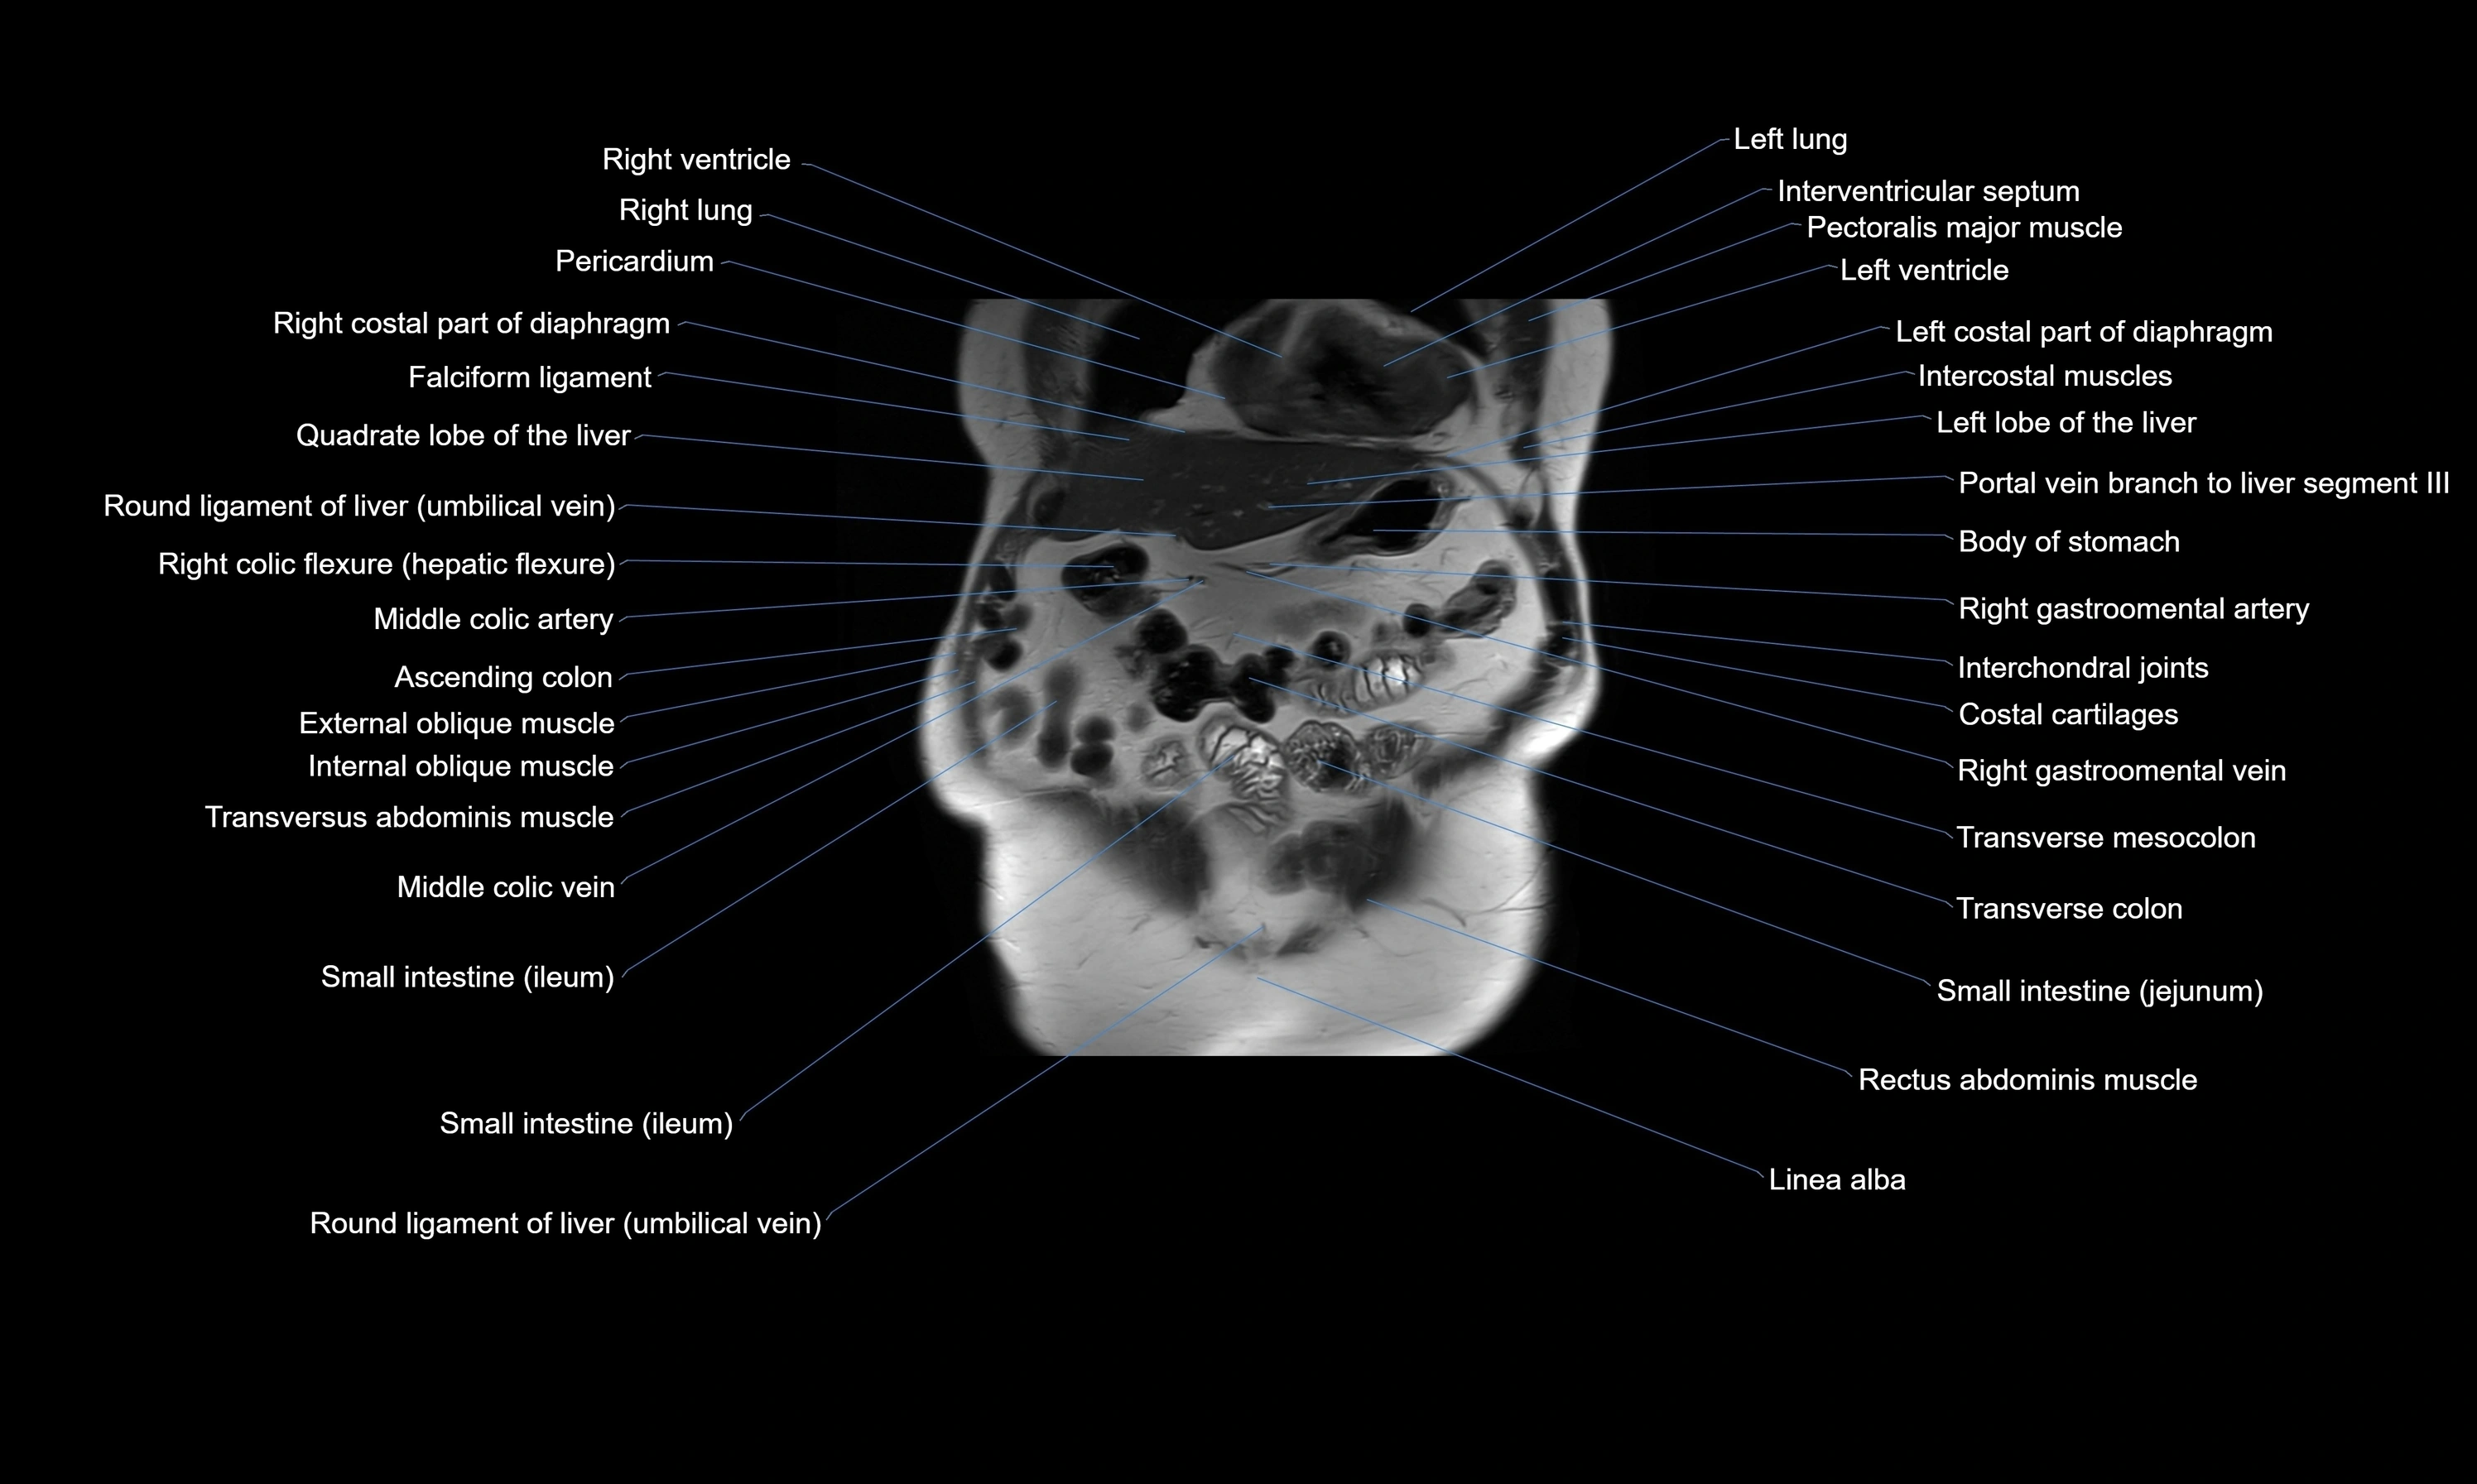

CT images